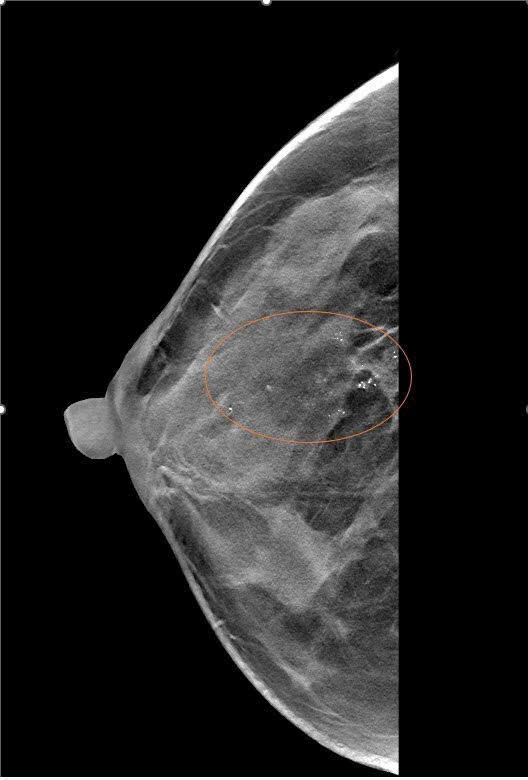

Hà Nội – Khi bác ruột được chẩn đoán mắc ung thư vú, chị P và mẹ quyết định đi tầm soát để kiểm tra sức khỏe. Ban đầu, chị chỉ coi đây là một biện pháp phòng ngừa, nhưng kết quả sinh thiết đã khiến cả gia đình bất ngờ: chị P cũng bị ung thư vú giai đoạn đầu.

Theo báo cáo từ Trung tâm vú Mammocare Hà Nội, trường hợp của chị P không phải hiếm gặp. Ung thư vú đang có xu hướng trẻ hóa, không chỉ xảy ra ở phụ nữ trên 50 tuổi mà còn ở những người dưới 40, thậm chí dưới 30. Đáng nói hơn, nhiều bệnh nhân phát hiện bệnh khi chưa có triệu chứng rõ ràng.

Bác sĩ tại Mammocare khuyến cáo, tầm soát ung thư vú định kỳ là cách tốt nhất để phát hiện sớm và điều trị kịp thời. Khi được phát hiện ở giai đoạn đầu, tỷ lệ chữa khỏi có thể lên đến 90%.